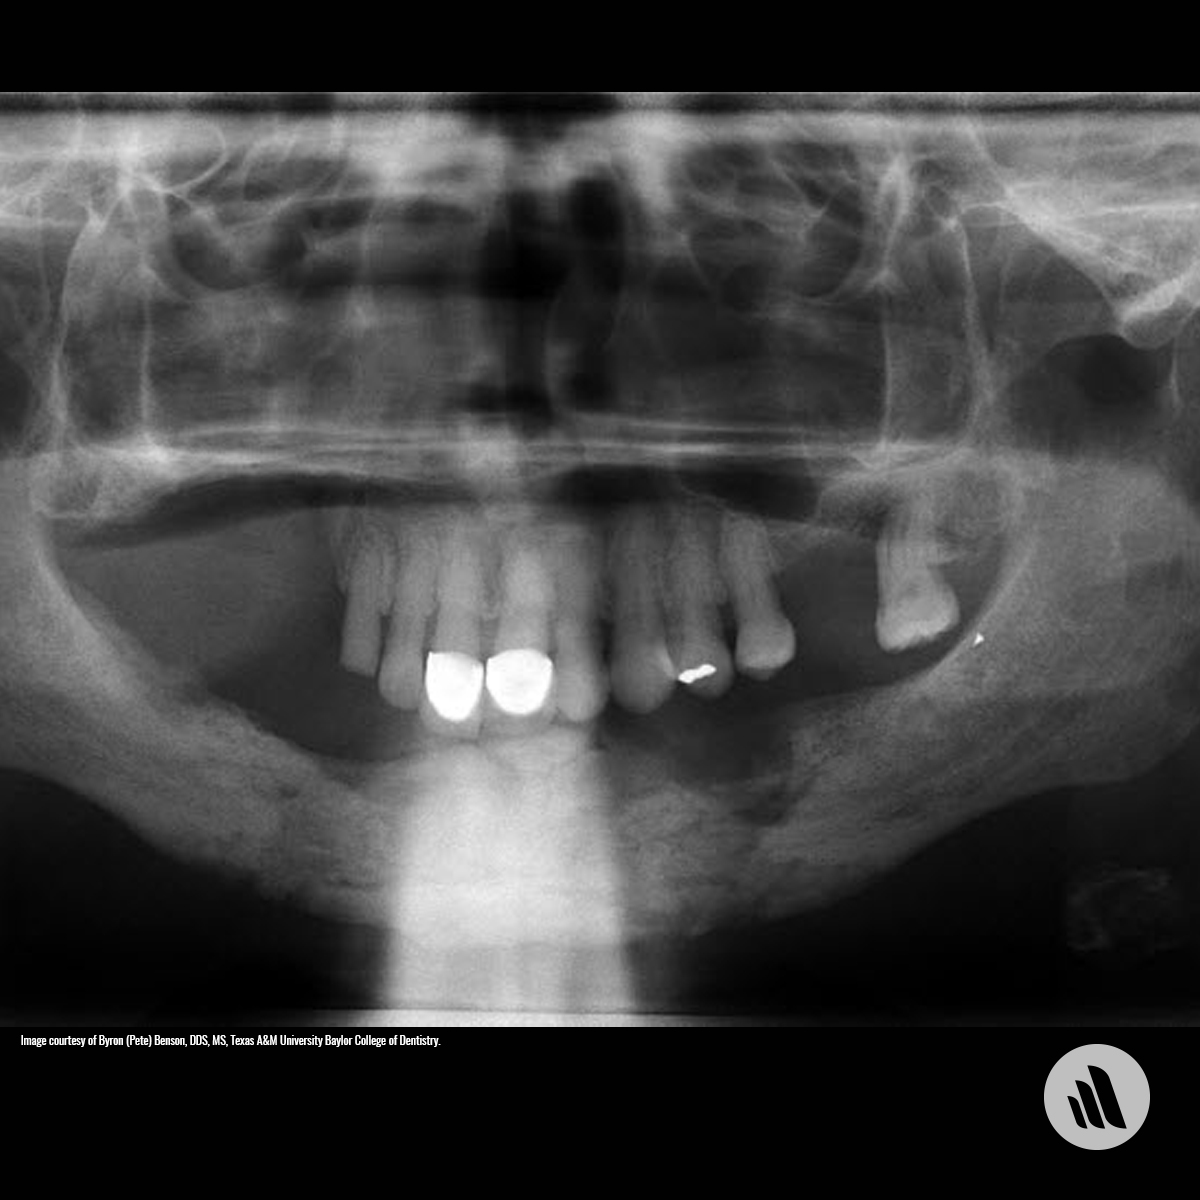

Флегмона Зубов Фото

Флегмона Зубов Фото 83 фотографий